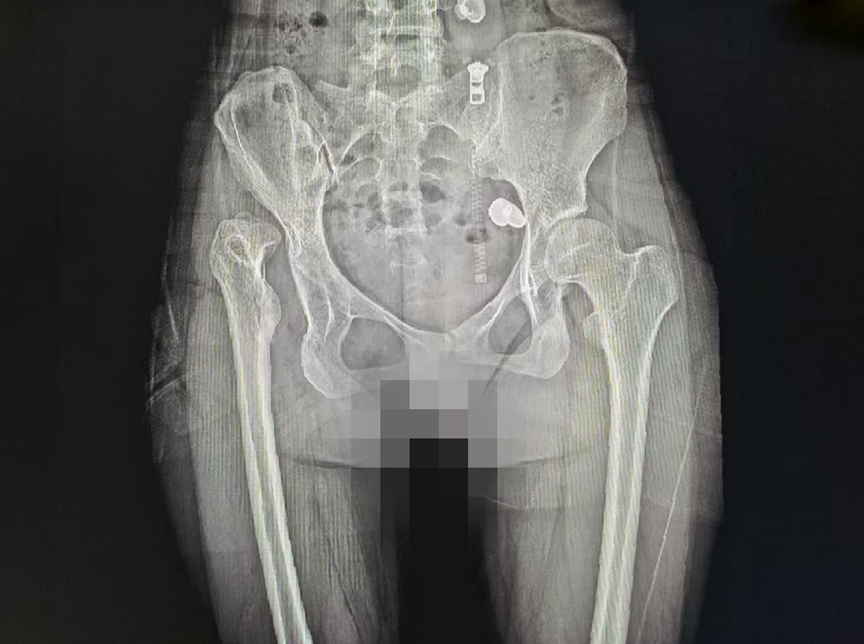

术前

入院后,医院手术团队第一时间为小舒进行了全面、细致的检查,结合她的病情、身体状况及康复需求,量身制定了机器人辅助髋关节置换治疗方案。与传统手术不同,手术机器人可提前进行精准的术前规划,精准测算假体的大小、安装位置,避免了人工操作的误差;术中,机器人实时监测手术操作,全程辅助医生完成假体植入等关键步骤,既保证了手术的精准度,又最大程度减少了对周围组织的损伤,真正实现了精准、微创、不截骨。